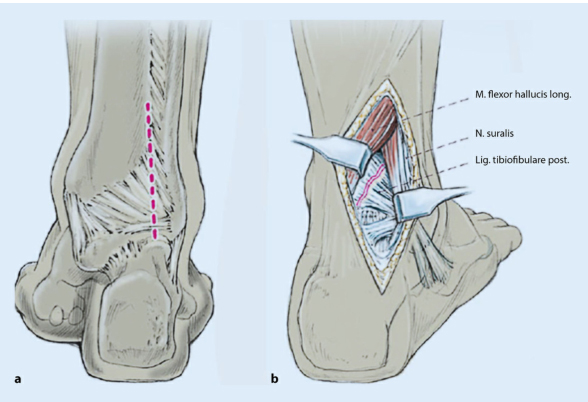

1). С биомеханической точки зрения, имплантация заднелатеральной пластины малоберцовой кости и пластины заднелатеральной лодыжки посредством заднелатерального доступа может обеспечить более стабильную фиксацию при трехлодыжечных переломах.

2). Преимуществом заднелатерального доступа является хороший охват мягких тканей имплантата. (Следующий рисунок).

Техника фиксации пластин. Пластина сначала фиксируется к проксимальному сегменту малоберцовой кости (а), а затем ввинчивается стягивающий винт в качестве инструмента дистальной редукции (б). ПРИМЕЧАНИЕ. Убедитесь, что пластина не достигает верха малоберцовой кости, чтобы не раздражать малоберцовое сухожилие.

разрез кожи